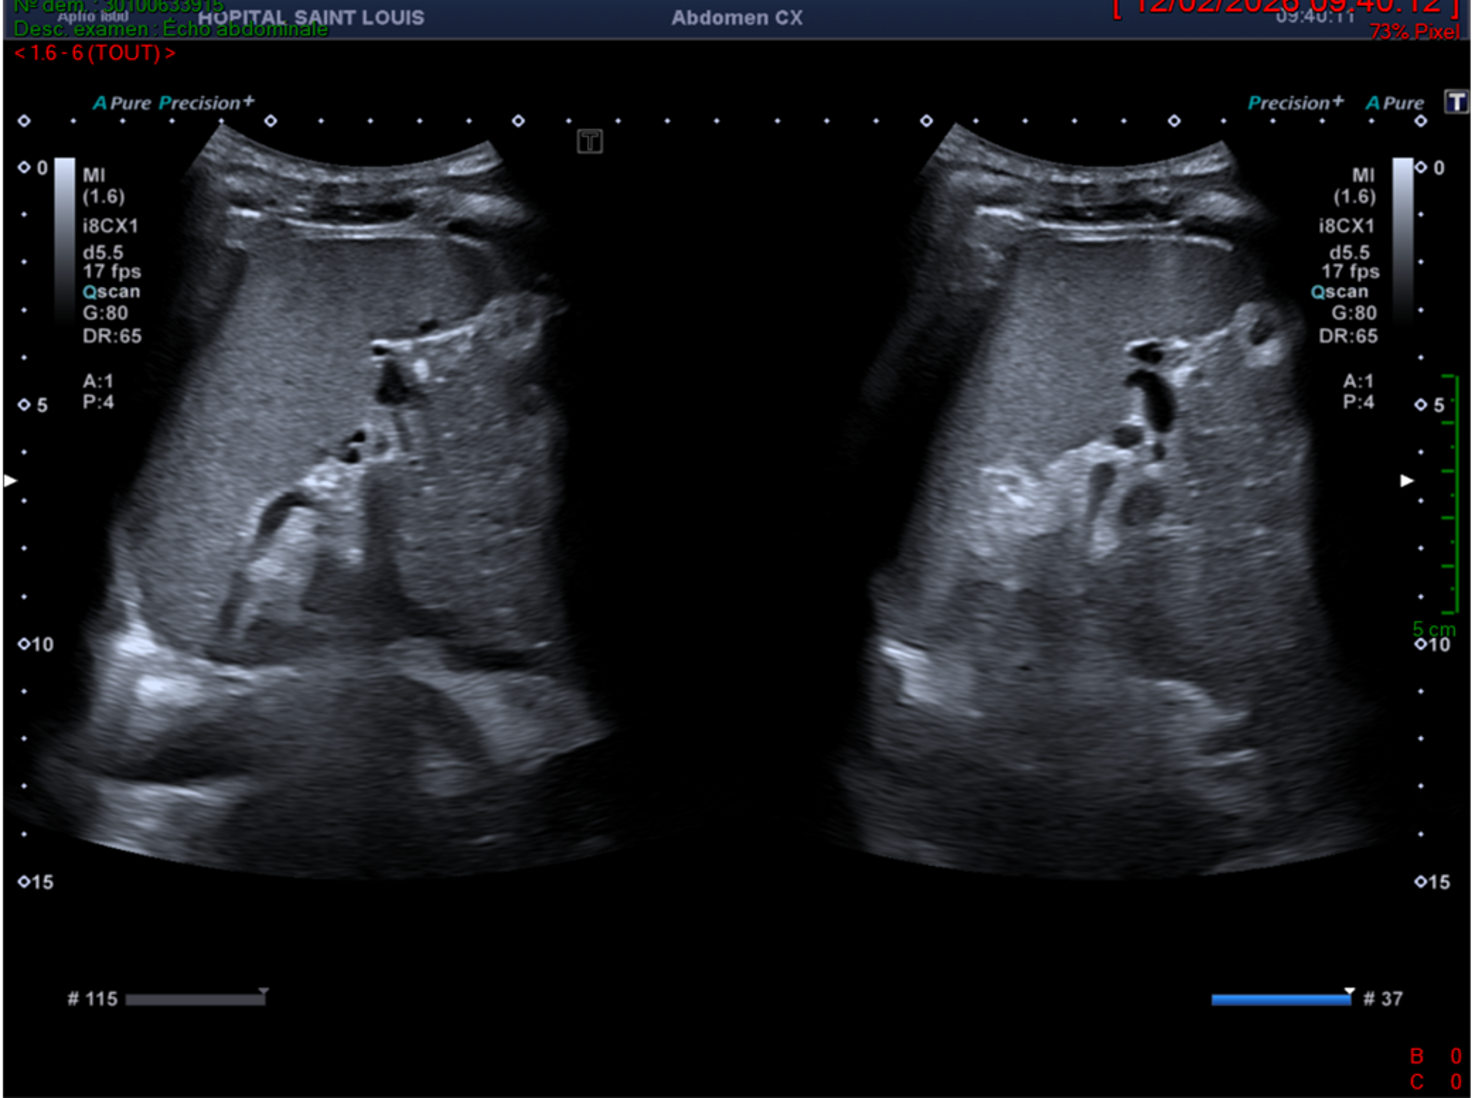

L’échographiste utilise une sonde convexe abdominale de basse fréquence pour réaliser l’examen et détecte un foie homogène, augmenté de taille, sans lésion focale.

Ici, la flèche hépatique est mesurée devant le rein droit, elle aurait pu être mesurée sur la ligne médio claviculaire droite.

Le morphotype du patient (longiligne, bréviligne…) doit être pris en considération avant de conclure à une hépatomégalie.